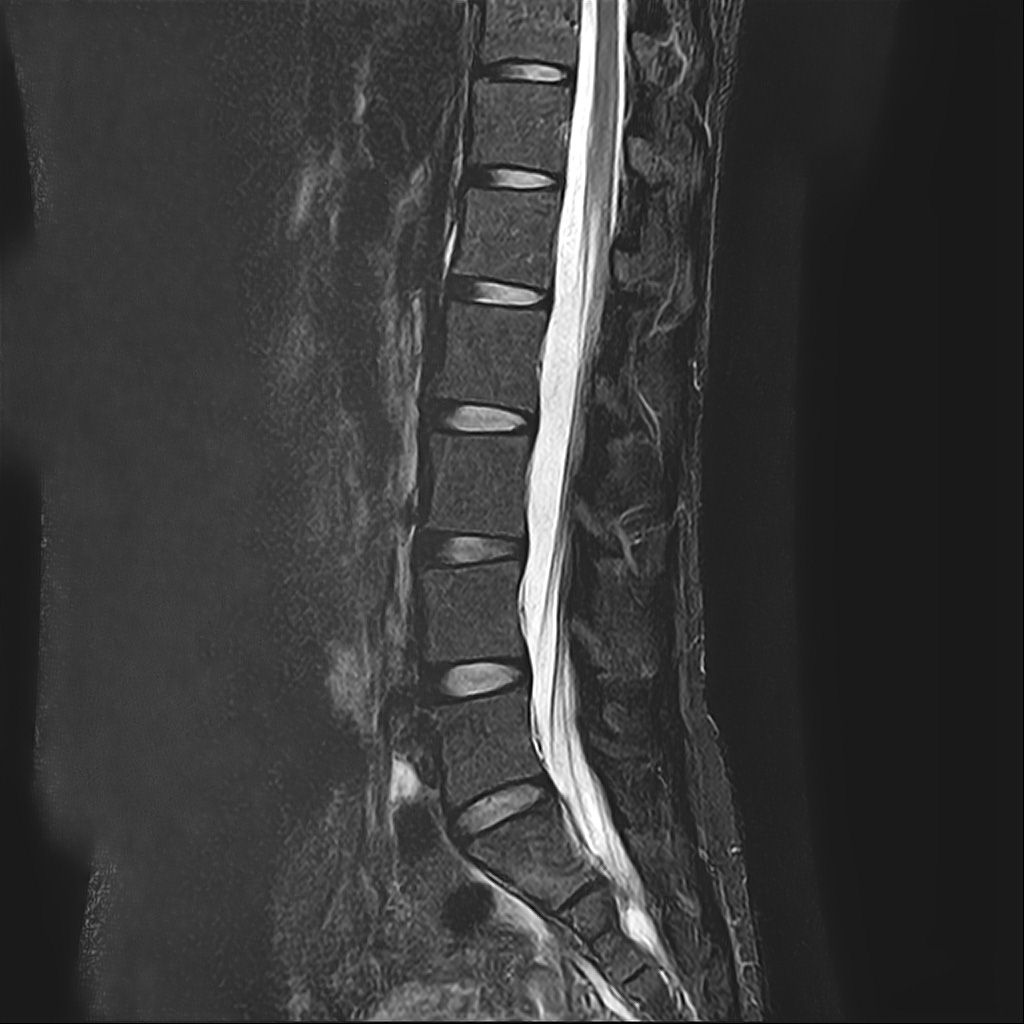

낭종s1-3번까지 꼬리뼈쪽으로 크게 나있다고했고, 단면상으로는 s2,3번이 촬영이 안되서 확인이안된다합니다. 허리디스크가 미약하게 4,5번에 있다고 했는데,

• 3번 째 사진